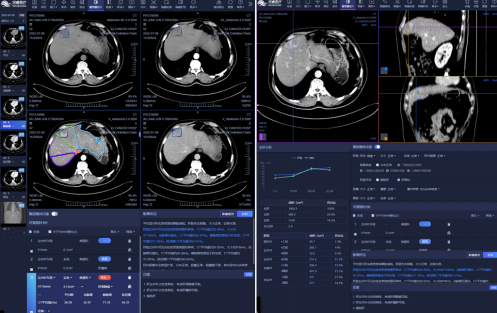

肝结节的检出及定量分析:AI软件检出肝脏病灶后,可以提供病灶的位置、体积、强化曲线等量化信息,并辅助定性;评估肝内胆管有无扩张、门静脉有无癌栓,辅助诊断有无脉管累犯;可以自动识别肝段,提供各个肝段及左右肝、全肝的体积信息,用以评估残肝体积比及辅助制定手术方案。